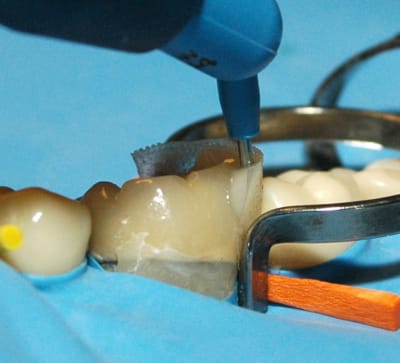

Enfin, sur l'image, on a utilisé des anneaux . Si les anneaux servent à plaquer la matrice contre la dent concernée, il agissent également comme écarteurs. Dans ce cas, c'est inutile. Pourquoi utiliser des anneaux, puisque l'on peut sans doute appliquer la matrice sur les parois axiales sans avoir besoin de tout cela. On gagnerait en visibilité et accessibilité.

Une fois la forme de la matrice figée, je pense qu'il faut la photopolymériser. Elle deviendra alors rigide, ce qui facilitera la mise en place du composite.

EverStick Net a existé en forme peu rigide, qui demandait un support d'adhésif pour la renforcer. Actuellement, le produit est modifié, il est souple, se laisse aplatir et de manipulation aisée.

Très facile à placer en interdentaire comme présenté sur les illustrations, à la limite il n'est pas utile de conserver un maximum d'émail, pour être sur que les anneaux puissent se caler. Un bon espace = une mise en place simple de la matrice. Elle peut également être découpée en bandelette,ainsi, être utilisée de manière conventionnelle.( très pratique pour les grands délabrements qui rendent l'usage de l'anneau impossible ).